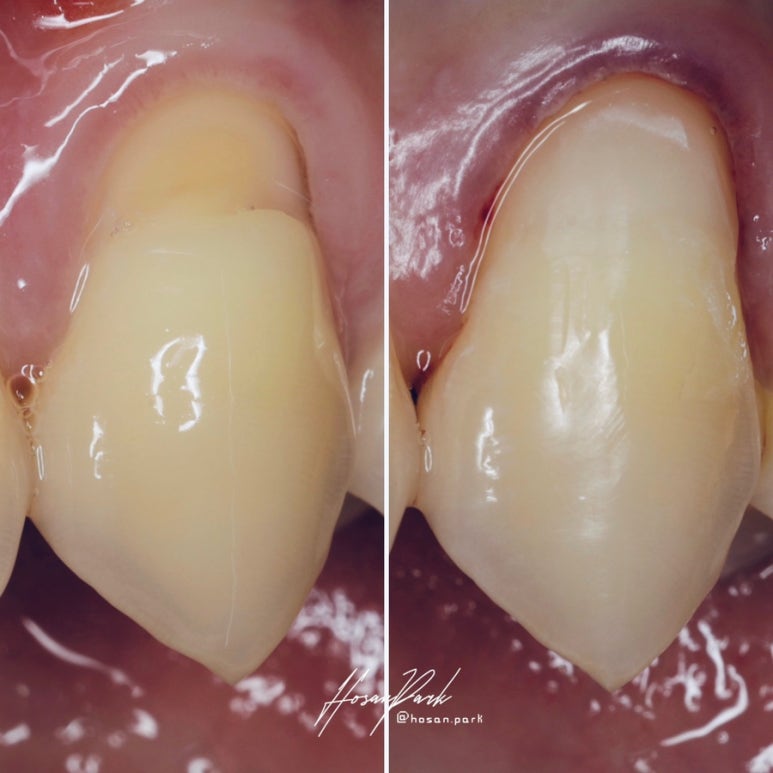

치경부 마모증 레진 수복 증례

좌측이 술전 사진인데요. ‘치경부 마모증(cervical abrasion)’이라고 하서 치아의 뿌리와 머리의 경계 부분인 치아의 목 부분이 쐐기 모양으로 파이는 상황이랍니다. 오른쪽은 레진 수복을 완료한 후의 모습입니다. 꽤 감쪽같이 복원되었죠?

저렇게 파여서 상아질이 노출되면 치아 내부의 신경과 점점 가까워지기 때문에 시린 증상이 생길 수 있고, 상아질은 법랑질보다는 강도가 훨씬 약하기 때문에 파이는 정도가 가속화되어 점점 더 심해지게 된답니다.